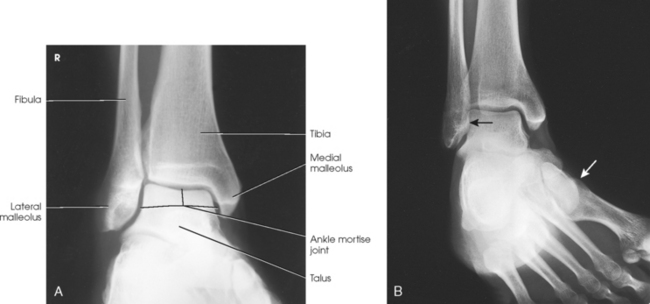

Structures shown: The entire ankle mortise joint should be shown in profile. The three sides of the mortise joint should be visualized (Figs. 6-102 and 6-103).

Fig. 6-102 AP oblique ankle, 15- to 20-degree medial rotation to show ankle mortise joint. A, Properly positioned leg to show mortise joint. B, Poorly positioned leg; radiograph had to be repeated. The foot was turned medially (white arrow), but the leg was not. Lateral mortise is closed (black arrow) because the “leg” was not medially rotated.

Fig. 6-103 Axial drawing of inferior surface of the tibia and fibula at the ankle joint along with matching radiographs. A, AP ankle position with no rotation of the leg and foot. Drawing shows lateral malleolus positioned posteriorly when leg is in true anatomic position. Radiograph shows normal overlap of anterior tubercle and superolateral talus over fibula (arrows). B, AP oblique ankle, 15- to 20-degree medial rotation to show ankle mortise. Drawing shows both malleoli parallel with IR. Radiograph clearly shows all three aspects of mortise joint (arrows). C, AP oblique ankle, 45-degree medial rotation. Radiograph shows tibiofibular joint (arrow) and entire distal fibula in profile. Larger upper arrow show wider space created between tibia and fibula as leg is turned medially for two AP oblique projections. This space should be observed when ankle radiographs are checked for proper positioning.